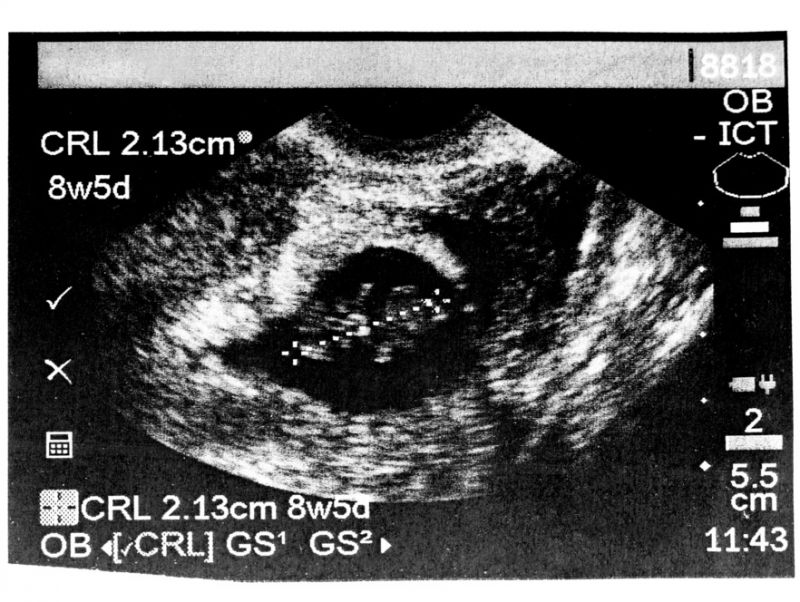

<a href="http://www.shutterstock.com/cat.mhtml?lang=en&search_source=search_form&version=llv1&anyorall=all&safesearch=1&searchterm=fetal+heartbeat&search_group=&orient=&search_cat=&searchtermx=&photographer_name=&people_gender=&people_age=&people_ethnicity=&people_number=&commercial_ok=&color=&show_color_wheel=1#id=25144666&src=52056c2a788bbf096d45c34beb9f0bfa-1-1">Cheryl Casey</a>/Shutterstock

Arkansas is the latest state to advance legislation that would significantly limit the time period in which women can legally obtain an abortion. On Wednesday, the state Senate’s Public Health, Welfare and Labor Committee approved a bill that would outlaw an abortion if a doctor can detect a fetal heartbeat—which can occur as early as six weeks into gestation.

Senate Bill 134 amounts to a near-total ban on abortion, as it often takes women six weeks to realize they are pregnant at all (especially when the pregnancy is unplanned). It would also cut off access to abortion well before fetal abnormalities or other conditions are apparent. More to the point, even finding a heartbeat that early in a pregnancy requires sticking a probe inside the woman’s vagina. This is basically Transvaginal Ultrasounds: The Sequel, except far worse, since it would deny a woman the right to have an abortion after having a plastic wand shoved inside her.

While the bill states that it would not subject women seeking an abortion to criminal charges, it would be a felony offense for any doctor to perform an abortion when a heartbeat is detectable. Sen. Jason Rapert, a Republican, says the bill is necessary because “[w]hen there is a heartbeat there, you have a living human being.”